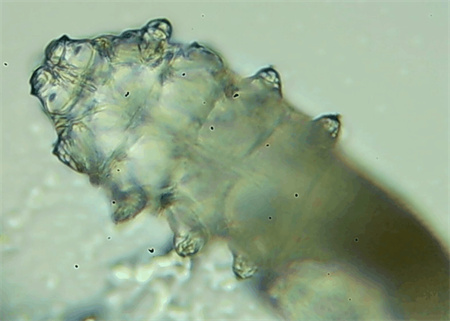

把玻片放到顯微鏡下觀察,通過電腦實(shí)時(shí)傳送的畫面,可以查看到這些拔下來的睫毛上是否有螨蟲。

結(jié)果,有6個(gè)人拔下來的睫毛上都發(fā)現(xiàn)了螨蟲。

這種螨蟲叫做蠕形螨,他們通常呈乳白色、半透明的細(xì)長狀,擁有四對(duì)腳。它們跟被子上的塵螨可不是同一種。

這些蠕形螨主要寄生在面部、頭皮、眼睛的睫毛毛囊、睫毛皮脂腺,以及瞼板腺里,以睫毛囊上皮細(xì)胞、腺體內(nèi)脂質(zhì)為食物。因此,即使經(jīng)常換洗床單、衣物,也可能會(huì)有蠕形螨。